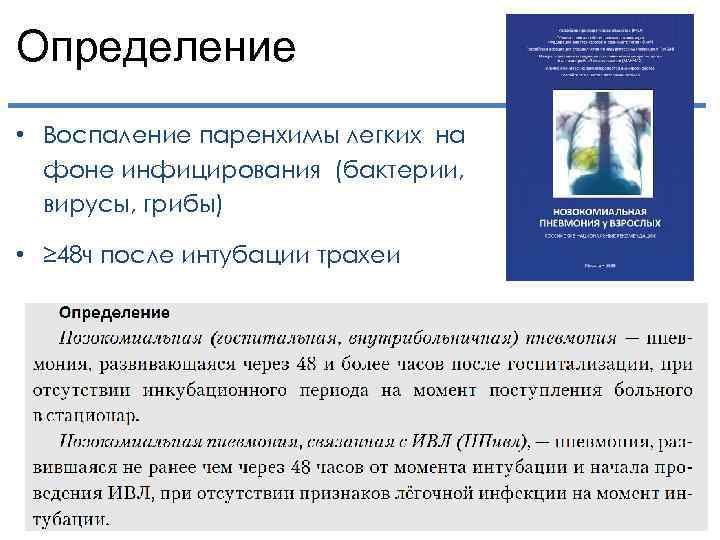

Определение • Воспаление паренхимы легких на фоне инфицирования (бактерии, вирусы, грибы) • ≥ 48 ч после интубации трахеи

Определение • Воспаление паренхимы легких на фоне инфицирования (бактерии, вирусы, грибы) • ≥ 48 ч после интубации трахеи